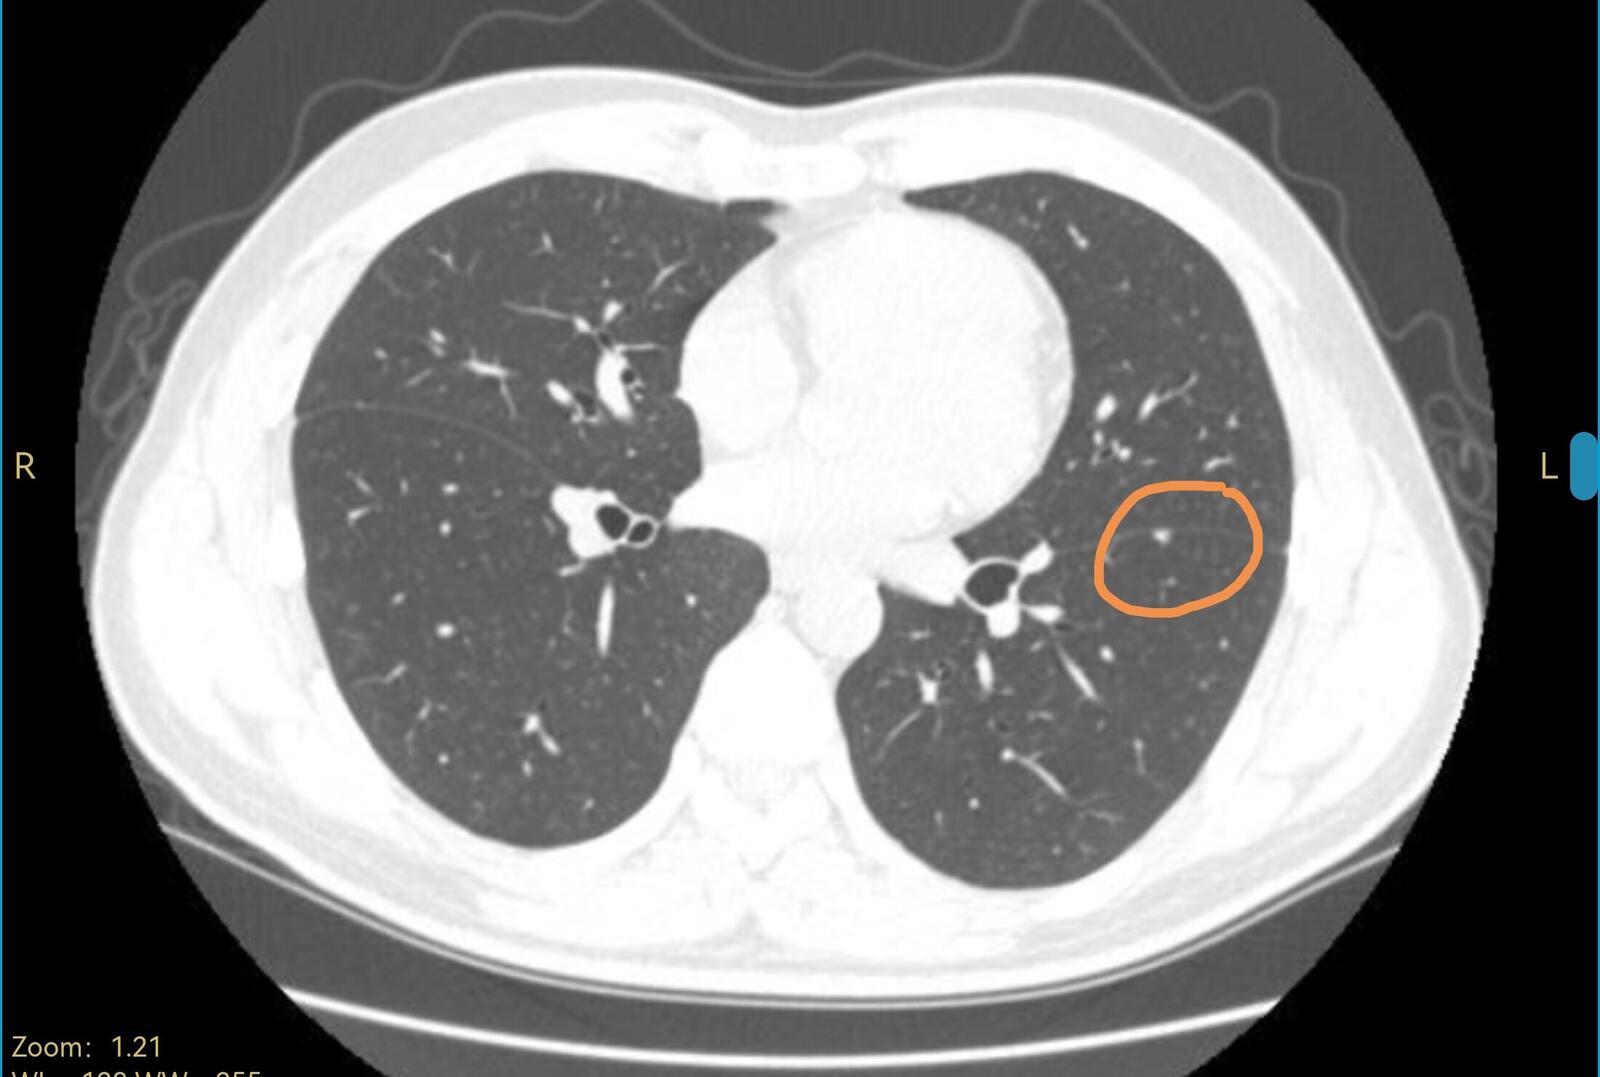

我看到了他的电脑图像,肺里面这两个结节,一左一右,都是在叶裂之间,直径都很小,右边那个结节是有钙化的,左边那个结节虽然没有钙化,但看起来像是个肺表面的淋巴结,这两个结节都考虑是良性,可以继续观察。CT上也没有其他可以解释胸口疼的表现,我请他再观察一下,也许不知道是怎么样抻了一下引起的疼痛。